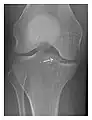

Occult osseous injuries may result from a direct blow to the bone by compressive forces of adjacent bones against one another or by traction forces during an avulsion injury. Lesions in the tibial plateau, hip, ankle, and wrist are often missed. In a tibial plateau fracture, any disruption of the posterior and anterior cortical rims of the plateau should be sought. Impaction of subchondral bone will appear as an increased sclerosis of the subchondral bone (Figure 1). In the hip, posterior acetabular fractures also present subtle radiographic findings. The acetabular lines should then be carefully examined keeping in mind that the posterior rim, which is harder to see on X-rays, is more frequently fractured than the anterior rim (Figure 2). In the wrist, detection of carpal bone fractures is often challenging, with up to 18% of scaphoid fractures radiographically occult. Carpal fractures, especially the scaphoid, are associated with the risk of avascular necrosis. In apparently normal wrist radiographs from symptomatic patients, if there is history of a fall on an outstretched hand with pain in the anatomic snuffbox, suggesting scaphoid injury, the initial examination with posteroanterior, lateral, and pronation oblique views must be complemented by other specific views such as supination oblique and the "scaphoid" view A careful examination of cortices for evidence of discontinuity or offset and cancellous bone for lucency is necessary (Figure 3).[1]

a

b

c

Figure 1: A 56-year-old woman presenting with left knee pain after a fall. (a) Initial anteroposterior radiograph was considered normal, however, subtle cortical disruption of the anterior rim of the medial tibial plateau, medial to the tibial spine, is noted (arrow). (b) Coronal T1-weighted MRI confirms the cortical disruption (arrow) and shows extensive fracture through the proximal tibia. (c) Coronal proton density-weighted image with fat saturation shows extensive edema in the subchondral bone. Note also hypersignal adjacent to the medial collateral ligament corresponding to a grade I sprain (arrowheads).[1]